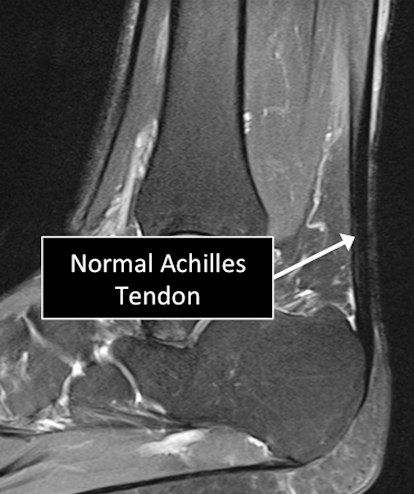

Ankle MRI examinations showing normal (top) and abnormal (bottom) Achilles tendon.

Why Translational MRI of the ankle?

- In the ankle, as in many other parts of the body there are certain structures that can’t be seen (they look black or dark) with the standard MRI.

- There are new “software” programs that allow us to see structures with different contrast (bright versus dark).

- Some of these “invisible” or dark structures are unique to the ankle (e.g. the Achilles tendon) and others are found in other parts of the body (e.g. cartilage, ligaments, other tendons, cortical bone).